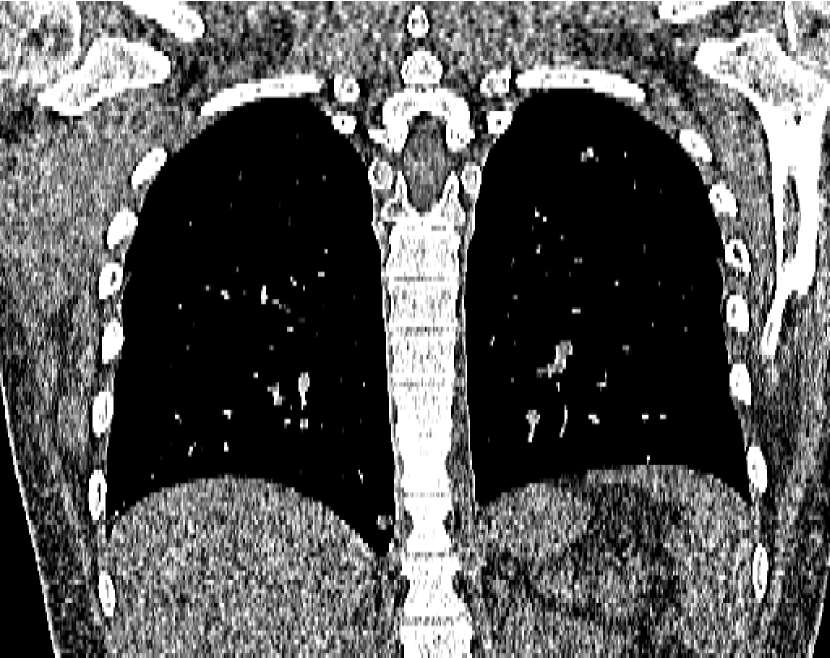

Refer to caption

(a) Clinical Standard Hybrid IR

(b) JENG

Figure 15: An example cross-plane image from the same thoracic dataset as in Fig. 14. (a) A coronal-view image slice of the clinical standard hybrid IR in soft tissue window. (b) JENG at a comparable resolution but with reduced image noise and artifacts.